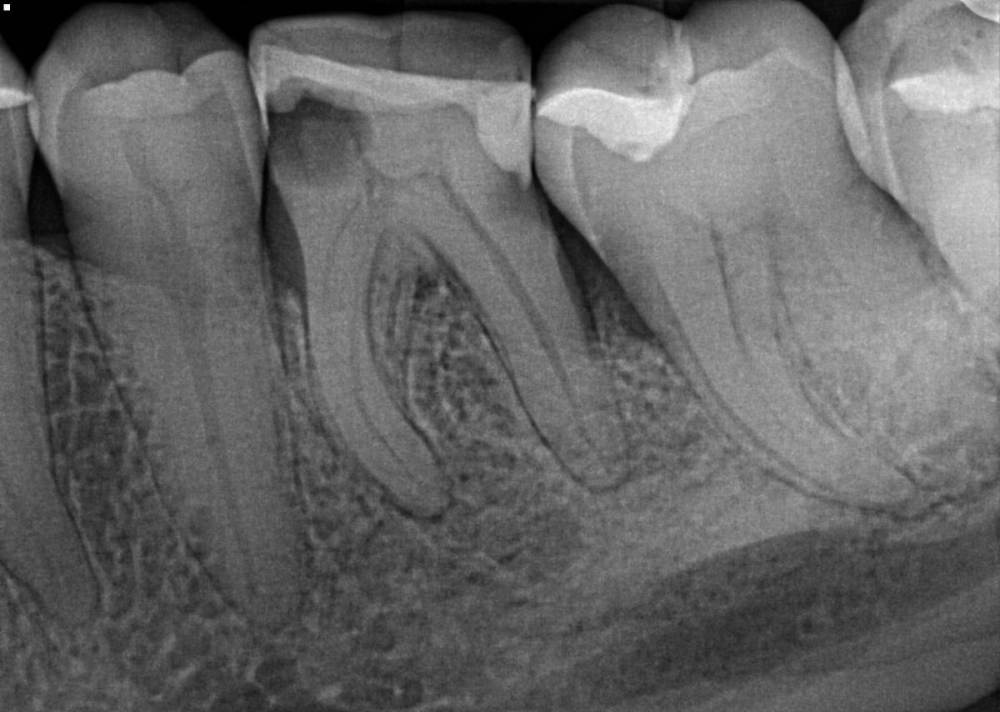

elenaterra Опубликовано 22 декабря, 2021 Автор Поделиться Опубликовано 22 декабря, 2021 Вот этот зуб где инструмент (и который тоже надо удалять она сказала), сверху белое это инструмент (якобы) Ссылка на комментарий

Notherbrick Опубликовано 22 декабря, 2021 Поделиться Опубликовано 22 декабря, 2021 7 часов назад, elenaterra сказал: Вот этот зуб где инструмент (и который тоже надо удалять она сказала), сверху белое это инструмент (якобы) Здесь все сложнее. Белое ( более контрастное) действительно похоже на обломок, но наверняка покажет только вскрытие. Что то конкретное по этому зубу можно сказать только при очном осмотре, но оптимизма, увы, не внушает. Ссылка на комментарий